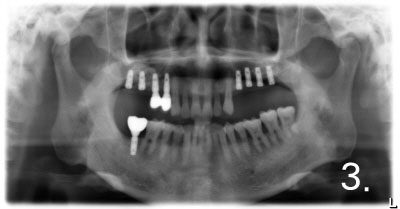

5. Immediate Loading after implant placement

Totally edentulous status on lower jaw

Fit surgical guide for precise implant placement

Removal of gum at exact site for implant placement with dental laser

Placing Implants

Connection of temporary cylinder for provisional bridge

Provisional bridge to use right after placing implants

This is after bonding provisional bridge. Patient can have strong teeth in a few hours